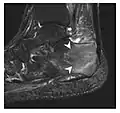

a

b

Figure 7: Fatigue fracture of the talus in a 25-year-old male basketball player with right hind foot and ankle pain, without history of trauma, and a normal initial radiograph (not shown). (a) One-month followup lateral radiograph shows normal appearance. (b) Sagittal T1-weighted MRI shows an irregular fracture line (arrow) within an ill-defined area of hypointensity corresponding to bone marrow edema.[1]